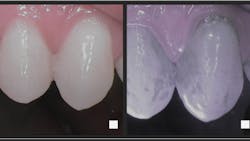

- Trujillo K, Räisänen IT, Sorsa T, Pätilä T. Repeated daily use of dual-light antibacterial photodynamic therapy in periodontal disease—a case report. Dent J (Basel). 2022;10(9):163. doi:10.3390/dj10090163